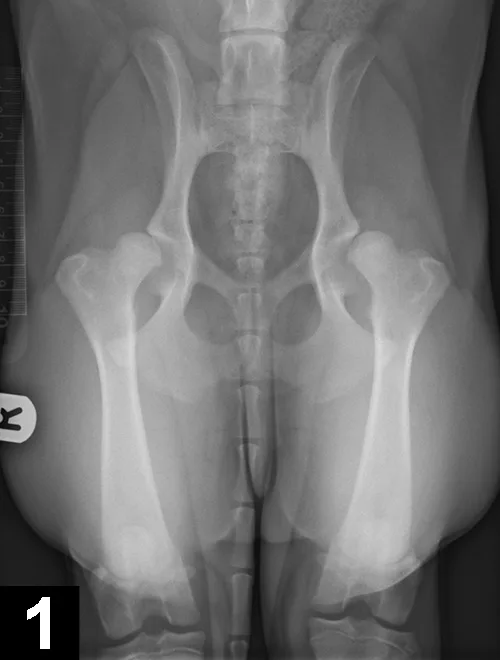

With this developmental disease, coxa vara (ie, decreased angle of inclination of the femoral head) and diminished anteversion angle (ie, less cranially oriented) of the femoral head result in medial displacement of the quadriceps mechanism. This muscular displacement results in abnormal forces that predispose the patella to luxate medially (Figure 7). MPL (95% of cases) is more common than lateral patellar luxation (LPL; 5% of cases); MPL especially affects small-breed dogs, although large-breed dogs may also be affected.1 Patellar luxation can be graded from 1 to 4, depending on the frequency of luxation and difficulty of manual reduction.

Ventrodorsal radiograph of the pelvis and hindlimbs in a 12-month-old Cavalier King Charles spaniel with MPL of the right stifle. Internal rotation of the tibial tuberosity is evident.